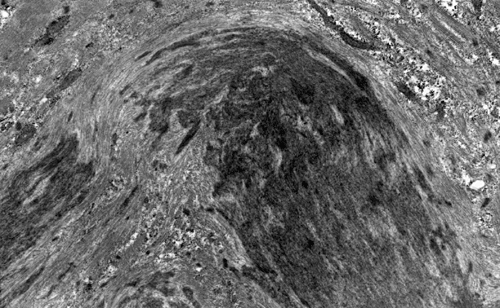

On hematoxylin-eosin stained sections, there is an increased variation of fiber diameter with many atrophic fibers intermingled with fibers of normal caliber. There is no evidence of fiber grouping or perifascicular atrophy. No inflammatory cells are present. There is also mild interstitial fibrosis (Panel A). On higher magnification, many fibers have a round concentric structure (Panel B). Irregular, centrally located depositions are also identified on modified Gomori's trichrome. The concentric nature, however, is not as obvious as in the hematoxin-eosin stained sections (Panel C). Type I and II fibers are not clearly separated in the ATPase preparation at pH 9.4. This is a common situation in chronically ill muscle (Panel D). The type I fibers are unusually dark. There is an increase in the proportion of type I fibers. The atrophic fibers are usually type II fibers. The concentric lesions are found predominantly in type I fibers (Panel E). There is an increase in PAS staining which is consistent with increased glycogen storage (Panel F). No increase in lipid content is demonstrated by oil red O (Panel G). On NADH-TR reaction, the concentric structures appear to have a clear central core that is devoid of enzymatic activity, a rim with intense enzymatic activity and a surround zone with relatively normal reactivity. These features are classic for target fibers (Panel H and I). No deficiency of laminin-2 (merosin) (Panel J) or dystrophin (Panel K) is demonstrated by immunohistochemistry. The central lesions are also immunoreactive for both laminin-2 and dystrophin. Immunohistochemistry for desmin demonstrate a core of strong immunoreactivity and also strong reaction in the sarcoplasmic membrane (Panel L and M). The target structures are also well demonstrated on semithin sections (Panel N). On electron microscopy, z-disc streaming is a common finding and they are often admixed with a substantial amount of dense granular electron dense substance (Panel O and P). There are also numerous cytoplasmic bodies characterized by radiating intermediate filaments (spheroid bodies) (Panel Q and R).

The two major pathologic findings are inclusion bodies and granulofilamentous material. Type I fibers are predominantly affected. Inclusions are eosinophilic on hematoxylin-eosin stain and bluish on modified Gomori’s trichrome stain. These inclusions are often negative for oxidative enzymes. A strong reactivity for desmin can be demonstrated by immunohistochemistry. The abnormal accumulation can occur as cytoplasmic inclusions, subsarcolemmal inclusions, spheroid bodies (10-20 mm oval or spherical inclusions), and patches or “hyaline structures”. In some cases, there is Z-disc streaming but no masses are demonstrated by trichrome stain. Numerous negative areas may be demonstrated by oxidative enzyme reactions. An accentuated intermyofibrillar network is seen by antidesmin antibody staining. Under the electron microscope, spheroid bodies appear as cytoplasmic bodies with a dense, granular core surrounded by fine filaments in a coronary arrangement. Although they are conspicuous on light microscopy, they may not be as distinctive at the ultrastructural level.

Granulofilamentous materials, also known as dappled dense structures” are dense anatomosing and trabeculated granular material that is about 100 nm in diameter is accumulated in between myofibrils or under the sarcolemma. The Z-disc streaming may appear contiguous to the granular deposits. They also appear as “non-hyaline” structure on immunofluroesent microscopy.Cytoplasmic bodies characterized by radiating intermediate filaments (spheroid bodies) are also common.